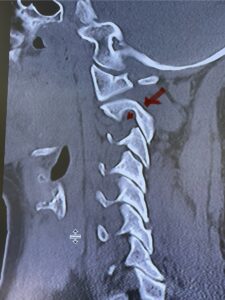

Fig. 6a: Sagittal cervical CT scan demonstrating an abnormally thin right C2 isthmus prohibiting safe placement of screw (red arrow). Notice the vertebral foramen eroding the isthmus bone structure (red dot).

Cervical x-rays revealed a significantly increased atlanto-axial interval (Fig. 5) On review of her imaging studies it was noted that the right C2 isthmus was very thinned by the vertebral foramen (Figs 6a, b, and c) which would make an attempt at placing a C2 pars screw dangerous. A decision was made to perform an occipital-cervical fusion because only possible unilateral fixation and an extensive C1 laminectomy to be performed eliminating a fixation point if a more traditional C1-C2 was performed. Even if C1 lateral mass screws were able to be placed one could only perform a unilateral screw construct fixation to C2. We performed an occipital cervical fusion down to C4 to get enough inferior fixation and C1 laminectomy. The decompression went well. We placed a left unilateral pars screw and bilateral C3 and C4 lateral mass screws. We placed three 12 mm screws in the midline keel (Fig. 7). Postoperatively the patient had all around improvement in her symptoms and did not qualify for rehab. Her post op films at 6 weeks (Fig. 8)